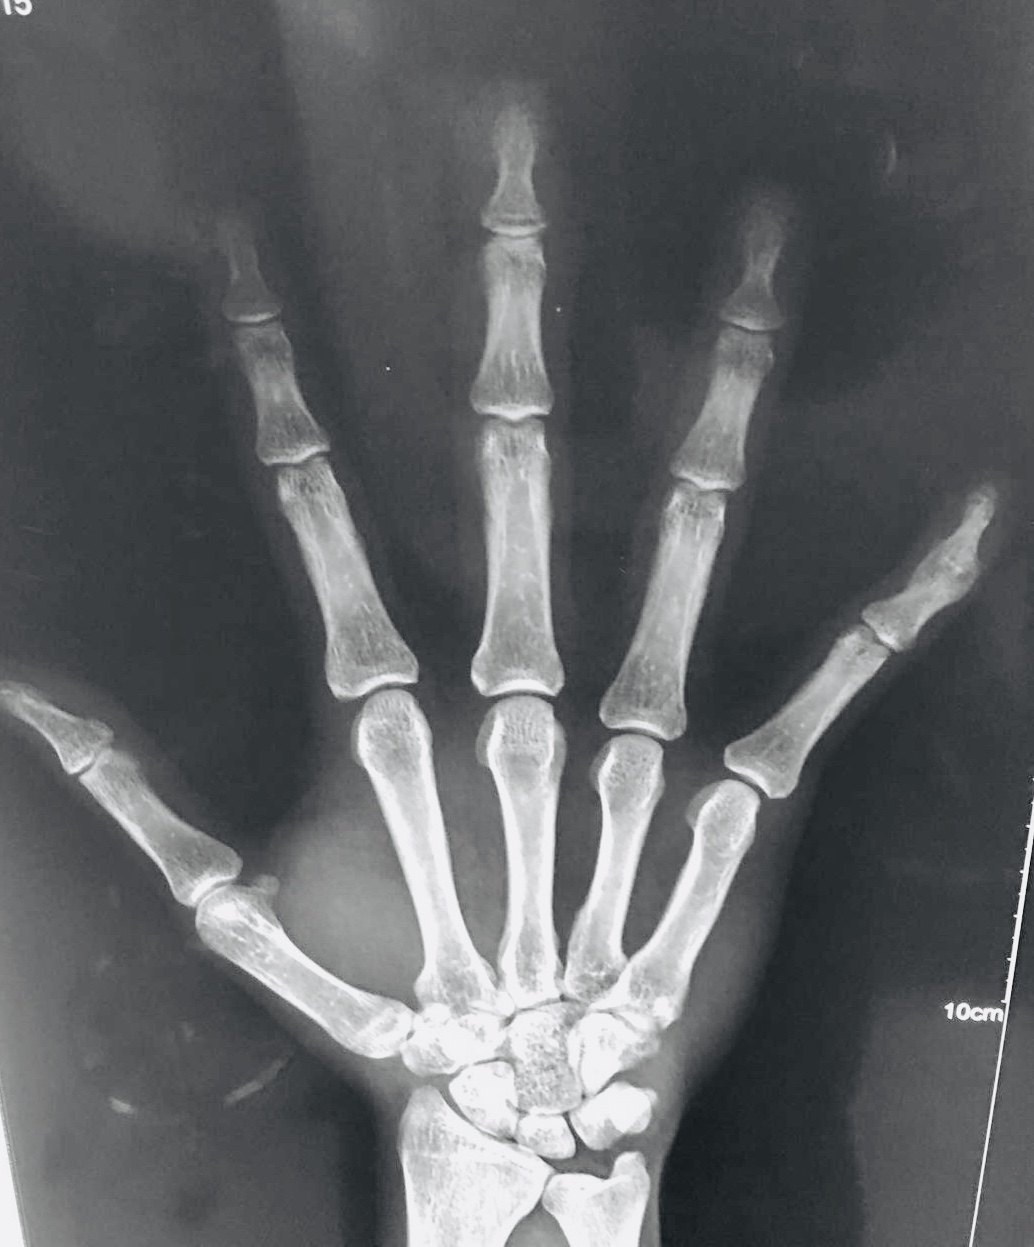

指骨骨折

图片尺寸640x853